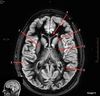

Image weighting and axis

T2 Axial

A

Basal Ganglia

B

Posterior horn lateral ventricle